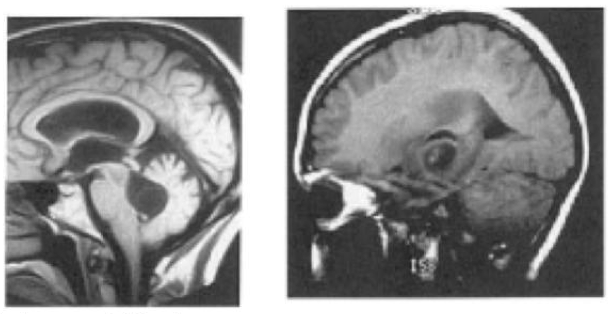

perhatikan gambar! diagnosis manakah yang paling mungkin (MRI T1-tertimbang)

A. Ensepalitis Herpes simpleks

B. Meningitis Bacterial

C. Glioma Ganas

D. Kokidiodomikosis

E. Limpoma

A